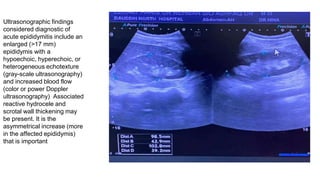

Ultrasonographic findings

considered diagnostic of

acute epididymitis include an

enlarged (>17 mm)

epididymis with a

hypoechoic, hyperechoic, or

heterogeneous echotexture

(gray-scale ultrasonography)

and increased blood flow

(color or power Doppler

ultrasonography) Associated

reactive hydrocele and

scrotal wall thickening may

be present. It is the

asymmetrical increase (more

in the affected epididymis)

that is important